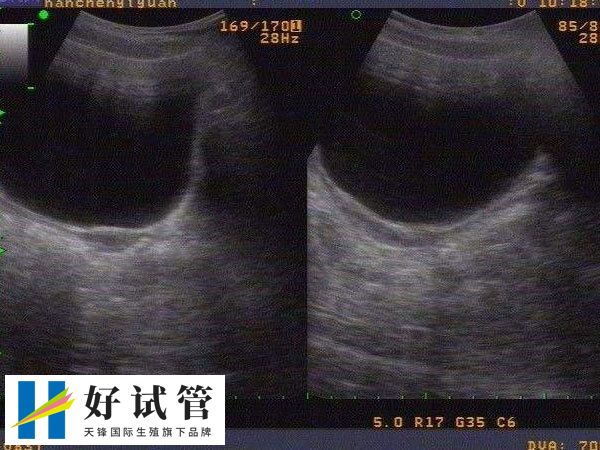

纵隔子宫能不能做试管婴儿

一般来说,纵隔子宫的女性可以进行试管婴儿,但需要先进行手术治疗以纠正子宫纵隔的情况。毕竟纵隔子宫可能导致子宫腔形态异常,增加流产和早产的风险。为了确保试管妊娠的安全和成功率,通常建议患者在进行任何医疗决策前,建议咨询专业的生殖医学专家,进行全面的身体检查和评估。

纵隔子宫怎么做试管婴儿

纵隔子宫患者能做试管婴儿。患者可以先尝试手术切除纵隔,等术后子宫恢复,如果患者输卵管通畅,卵巢功能正常,那么也可以尝试自然备孕。如果自然备孕失败,那么就只能进行试管婴儿助孕。但纵隔子宫患者在做试管婴儿前需要评估其生育能力:

纵隔子宫做试管婴儿的成功率

子宫是女性重要的生理器官也是女性的孕育生命的重要场所,对女性的身体健康和生育功能有着非常大的影响。那么纵膈子宫做试管婴儿成功率多高,对此感兴趣的可以参考下列内容:

- 纵隔子宫试管成功率约为40-48%,但成功率只能作为参考;

- 试管移植的成功率除了子宫问题外,还与胚胎质量、年龄等诸多因素有关,所以子宫纵隔的试管移植有多成功还不好说。其实子宫纵隔对试管移植的成功率影响不大,主要影响是怀孕后容易流产或早产。